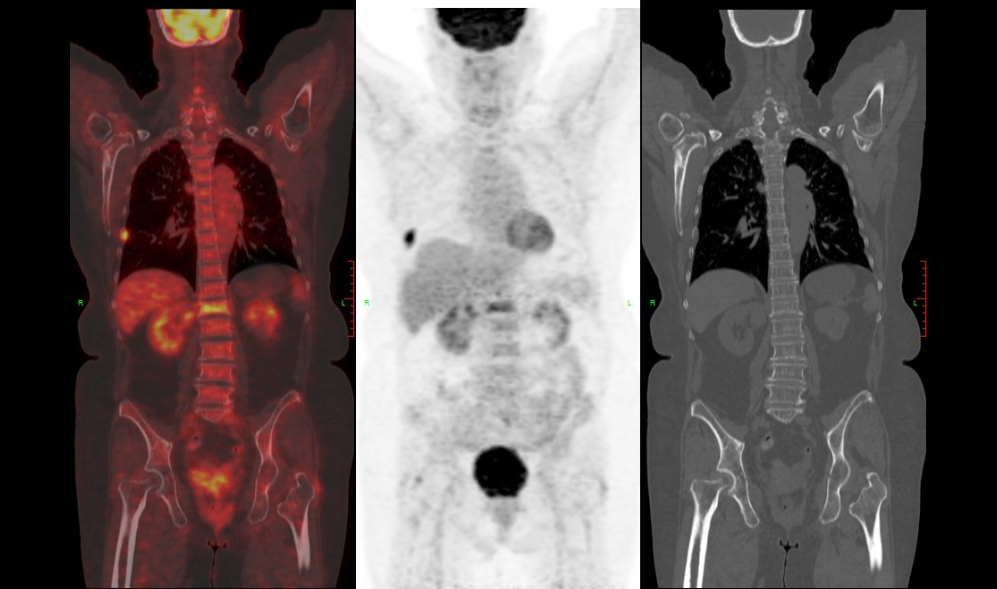

PET-CT:颈5、颈6、胸1椎体及附件、胸12椎体、右侧肱骨考虑MM改变,伴颈6椎体病理性骨折。

PET-CT结果:1.颈5、颈6、胸1椎体及附件、胸12椎体多发异常信号,符合MM改变,伴颈6椎体病理性骨折。2.颈椎退行性变:颈4~6椎体边缘轻度骨质增生,颈2/3-颈6/7椎间盘向后突出,颈4/5-颈6/7层面椎管及颈5/6、颈6/7双侧椎间孔变窄。3.胸椎退行性变:胸椎骨质增生,胸12/腰1椎间盘向后突出,胸7/8右侧、胸8/9左侧、胸9/10双侧、胸11/12及胸12/腰1左侧黄韧带肥厚,同层面椎管稍变窄。4.腰椎退行性变:腰椎骨质增生;腰2/3-腰4/5椎间盘向后突出,同层面椎管及双侧椎间孔狭窄。腰背部皮下软组织水肿

。5.右侧肱骨头软骨面下骨质侵袭,肩锁关节退变;右侧冈上肌腱远端、肩胛下肌肌腱I-II级损伤。6.右侧肱骨异常信号影,增强扫描可见强化,亦考虑MM改变,未排其他。